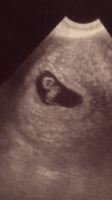

JuhuuI dag fikk vi se en sprellende peanøtt med bankende hjerte

Gyn ville ikke bruke dopler så tidlig. Målingene stemte med mine beregninger, 7+4